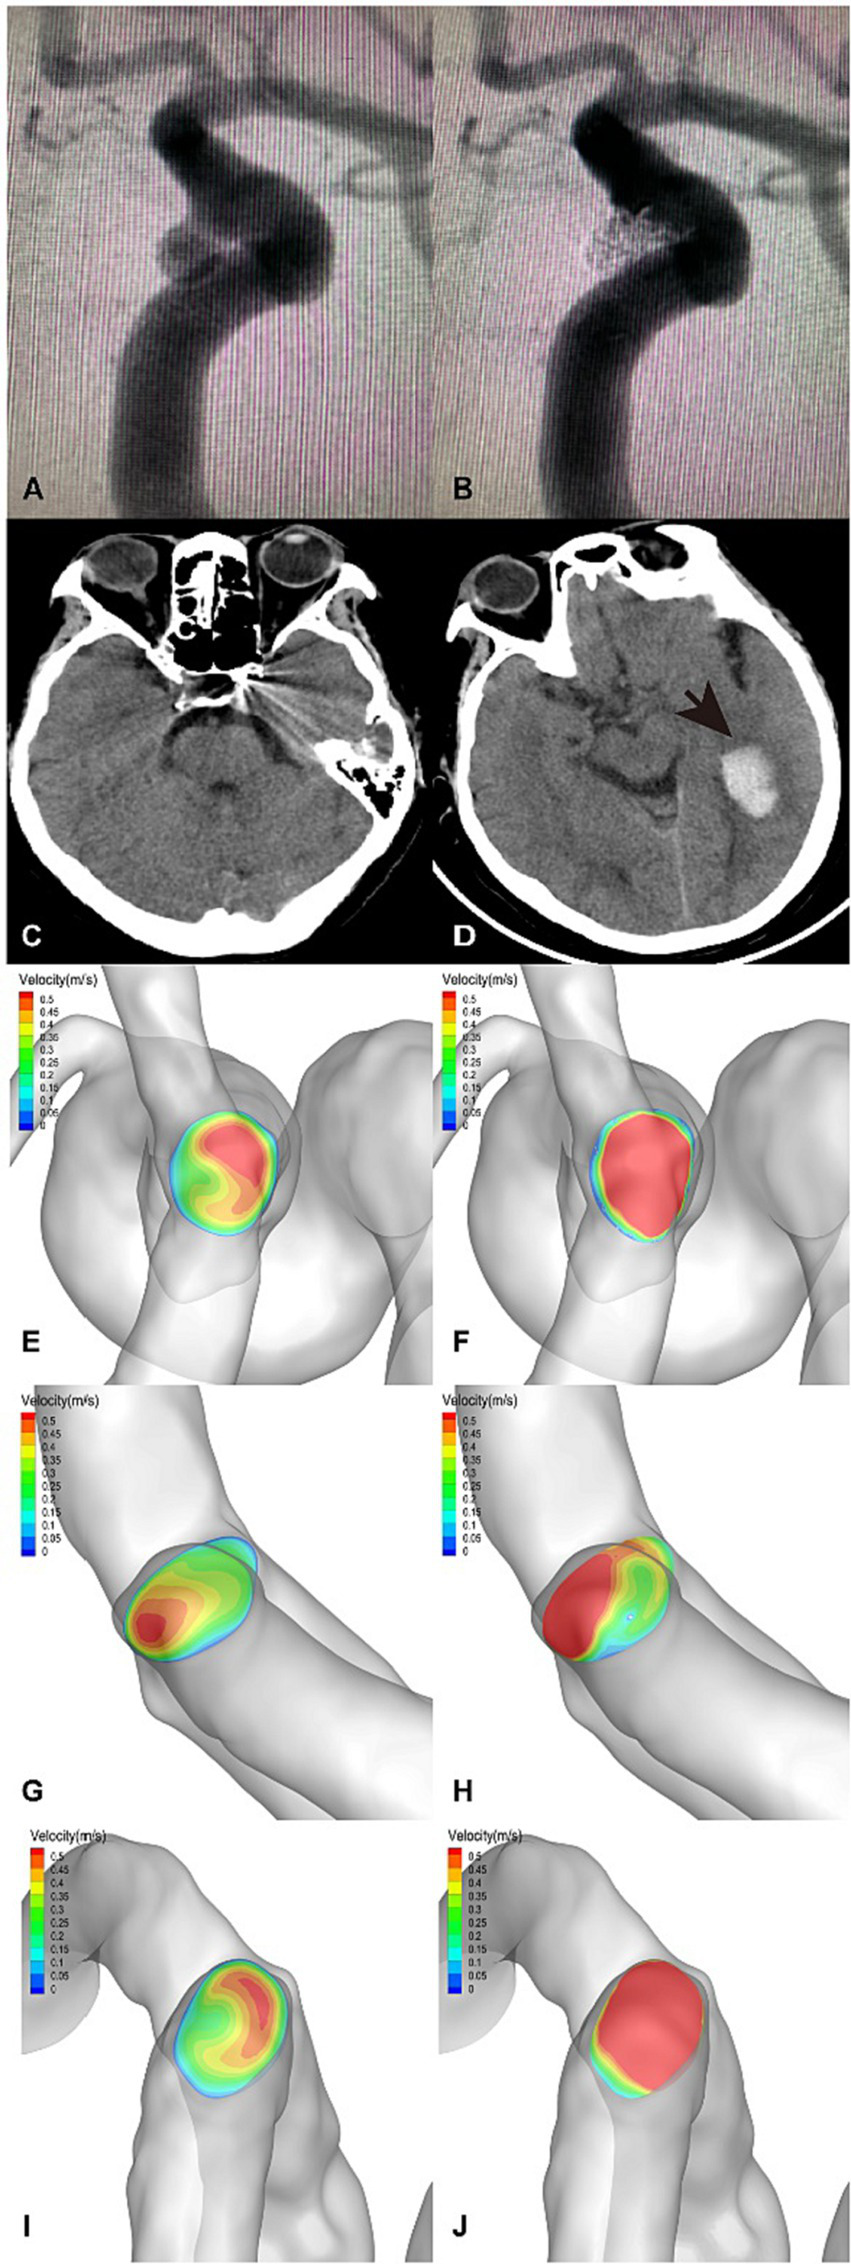

The flow velocity in the DICH-related artery (ACA) was significantly lower (as shown in Figures 4G,H), while the velocity in the DICH-unrelated artery (MCA) was higher (Figures 4I,J). Furthermore, remarkable infarcted areas were observed around the ipsilateral frontal lobe DICH on CT scans (Figure 4D), which were accompanied by a lower velocity in the DICH-related artery. Conversely, in type 2 DICH patients, the rate of velocity was notably higher in the DICH-related artery (MCA) (Figures 5I,J) compared to the DICH-unrelated artery (ACA) (Figures 5G,H). Additionally, flow velocity in all distal arteries (ACA and DICH unrelated MCA) was well-balanced and higher after SAC embolization in a patient from the control group (Figure 6).

Figure 4

A posterior communicating segment aneurysm of left ICA in DICH of type 1 was treated with EP2 stent assisted coiling. (A) Preprocedural angiography of the aneurysm and (B) postprocedural immediate angiography revealed Raymond grade 2. (C) The coiled aneurysm was showed by CT scan at 24 h later after the treatment. (D) CT scan obtained 4 days post-procedure, revealing ipsilateral frontal lobe DICH with surrounding infarcted area (asterisk). A significant increase in velocity was observed on the terminal section of the ICA (F) compared to the preoperative results (E) by computer hemodynamic detection (Increase rate was 44.9%). The velocity of DICH related artery (ACA) decreased significantly after embolization with increase rate of-35.9% (G,H), while the flow velocity of DICH unrelated artery (MCA) increased with increase rate of 35.7% (I,J). The imbalance index of this patient was 71.6%.